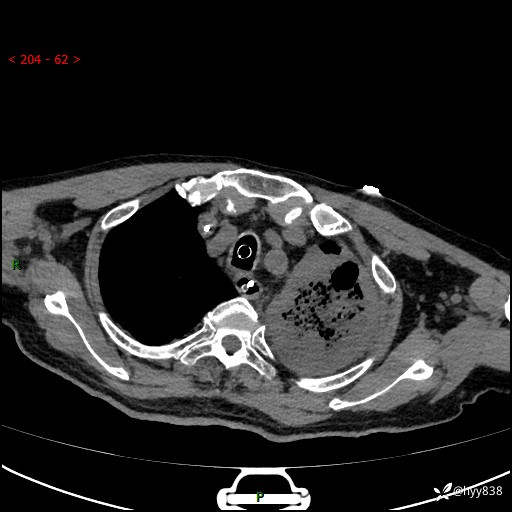

胸部CT平扫(2024.7.24)